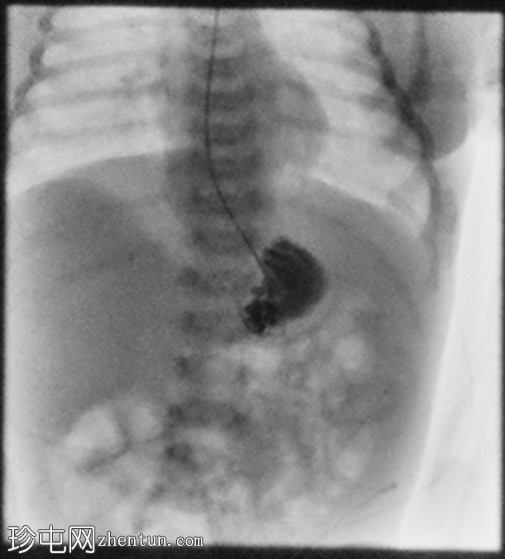

正位

延迟1小时拍摄的X线片显示食管裂孔疝和胃部仍有造影剂残留,造影剂远端扩散受限,很可能是由于造影剂用量较少所致。充满气体的肠袢外观正常,乙状结肠内可见气体,直肠内未见气体。